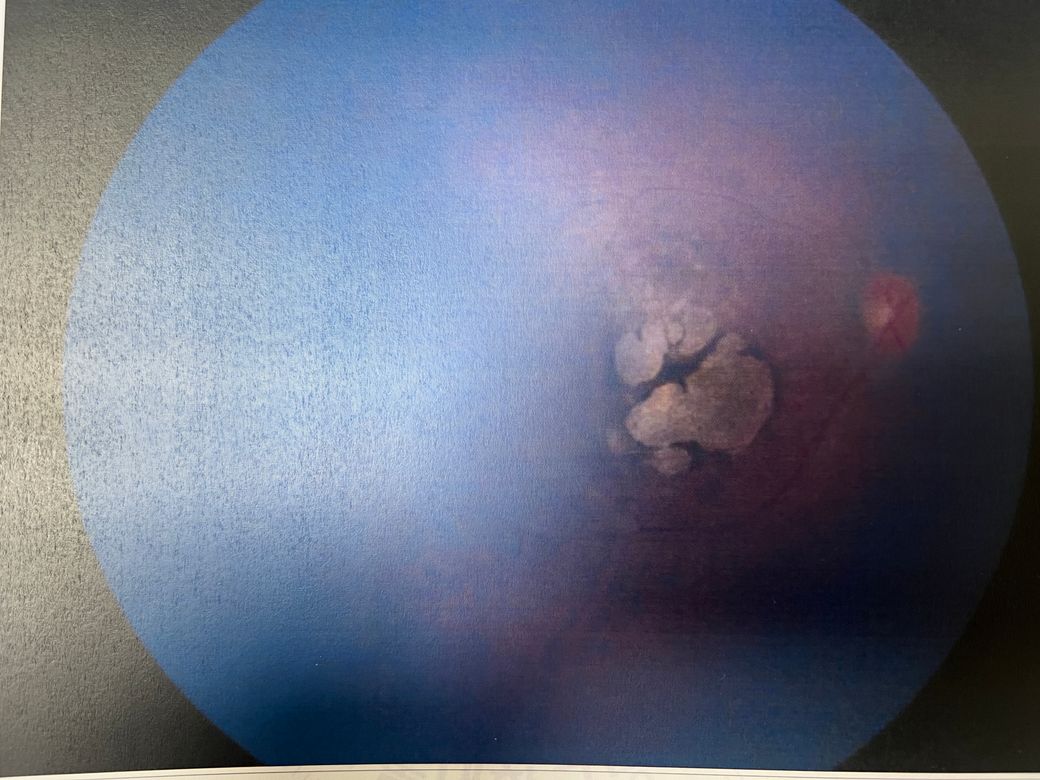

기다리는게 너무 답답해서 다른 대학병원 추가 검진 예정인데 오른쪽 왼쪽 안저검사 사진 첨부합니다.

• 2번 째 사진

우선 황반부 주변에 하얗게 보이는 부분 관련 황반부 시신경 부족이나 망막 변성을 의심할 수 있는 소견을 받으셨다 하셨고, 유전성 망막 질환(황반이영양증, 망막색소변성증 등)이 의심되고 있다구요.

이 경우 황반부 이상은 중앙 시야에 영향을 줄 수 있어 주의가 필요하지만, 정확한 심각성은 유전자 검사 결과와 추가 검진(OCT, ERG 등)을 통해 확인해야 합니다